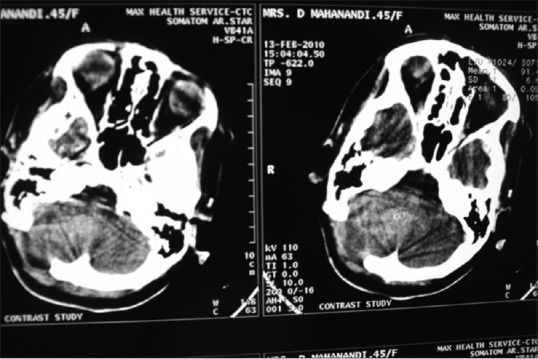

A 45-year-old female presented with headache, vertigo, and vomiting for the last 2 days and altered sensorium for the last 1 h. She had a past history of posterior fossa tumor and was operated 1 year back. Histologically, it was diagnosed as meningothelial meningioma of posterior fossa (WHO Grade I). Her hematological and biochemical tests were within normal limits except mild anemia. Electrolyte assay showed mild hyponatremia (Na-129 mmol/l). Computed tomography scan revealed a brightly contrast-enhancing dural-based mass at previously operated location [Figure 1]. Clinical and radiological diagnosis was recurrent meningioma. Her visual acuity was normal, but both the fundus showed papilledema. She had undergone repeat surgery, and intraoperative squash cytology was taken. The squash cytology revealed monotonous meningothelial cells arranged in lobules [Figure 2a]. There were some meningothelial cells with characteristic abundant cytoplasm and round nuclei pushing to periphery (rhabdoid cells) [Figure [Figure2b2b and andc].c]. In gross examination, the resected tumor was a grayish mass 5.5 cm × 4 cm × 3 cm. In histopathology, microscopy revealed a solid mass composed of meningothelial cells in sheets and in whorled pattern [Figure 3a]. There are areas of monomorphous sheets of cells with abundant eosinophilic cytoplasm with eccentrically placed vesicular nuclei and prominent nucleoli [Figure 3b]. The cells contained spherical masses of eosinophilic inclusions pushing the nuclei to the periphery. Areas of necrosis and psammoma bodies are also found. Mitotic count was 4–8/10 high power field. Final histopathological diagnosis was rhabdoid meningioma.